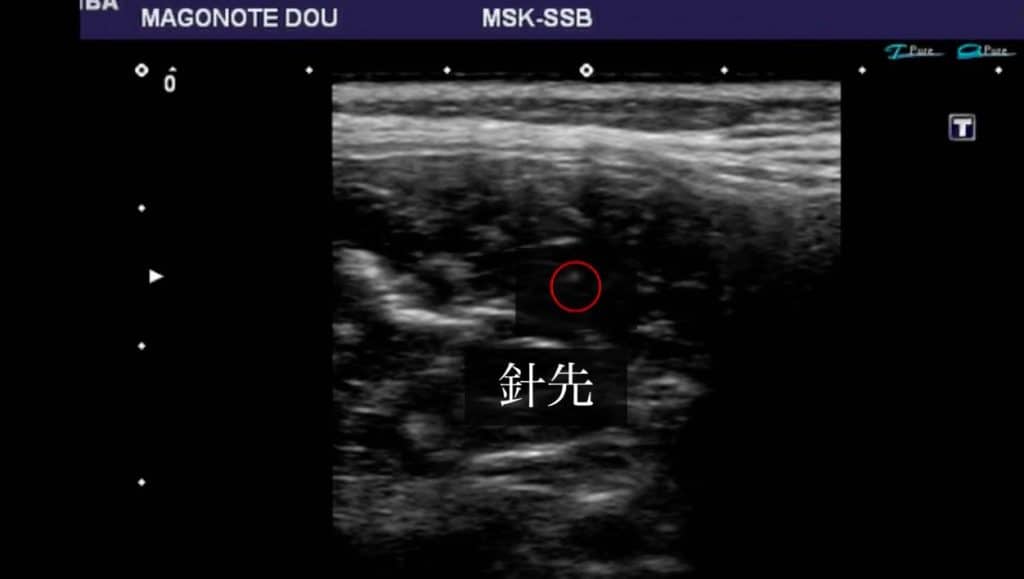

超音波エコーにて原因となる部位を観察します。

今回観察している部位は腰の筋肉内です。

痛みやしびれの原因となる部位、筋肉内の悪くなっているところは超音波エコー観察時ににて【白く】映し出されることが多いです。

その悪くなっている白い部位(筋膜の癒着部位)に鍼(はり)を刺して、くっついてしまっている部位を剥がし、痛みや痺れの改善に大きく繋げていきます。